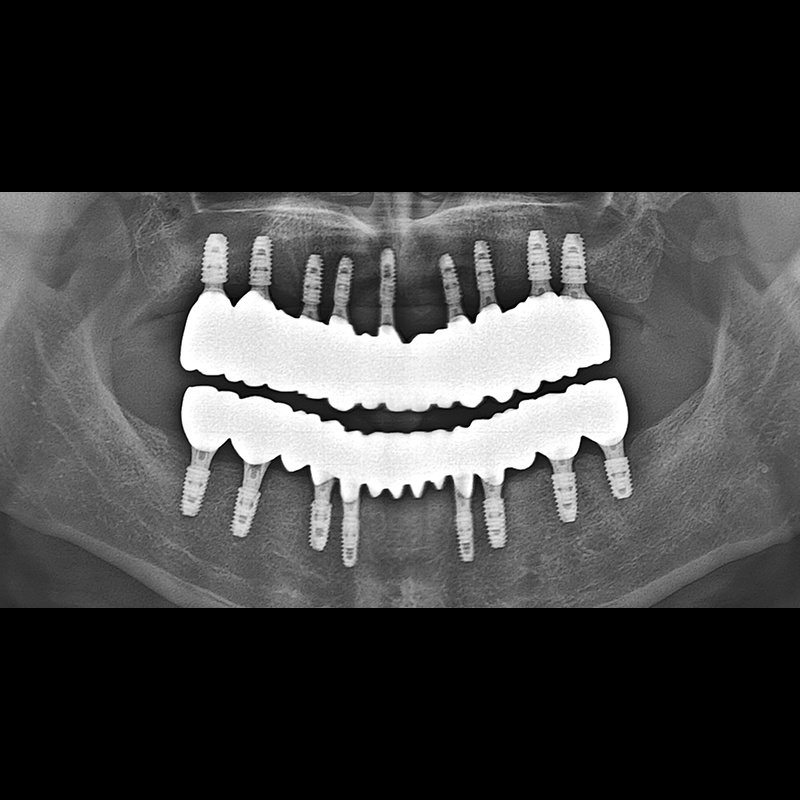

BEFORE AFTER

インプラント手術事例 2025.05.30

欠損した歯の部分と、生かしにくい歯の位置にインプラントを植立しました。